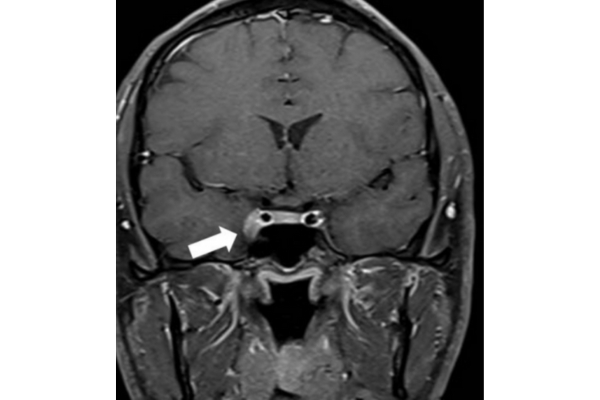

Tolosa Hunt Syndrome: Accurate Diagnosis and Effective Treatment Tolosa Hunt Syndrome (THS) is a rare disorder characterized by painful eye movements and headaches caused by inflammation of the cavernous sinus. As the condition can mimic other neurological diseases, an accurate…